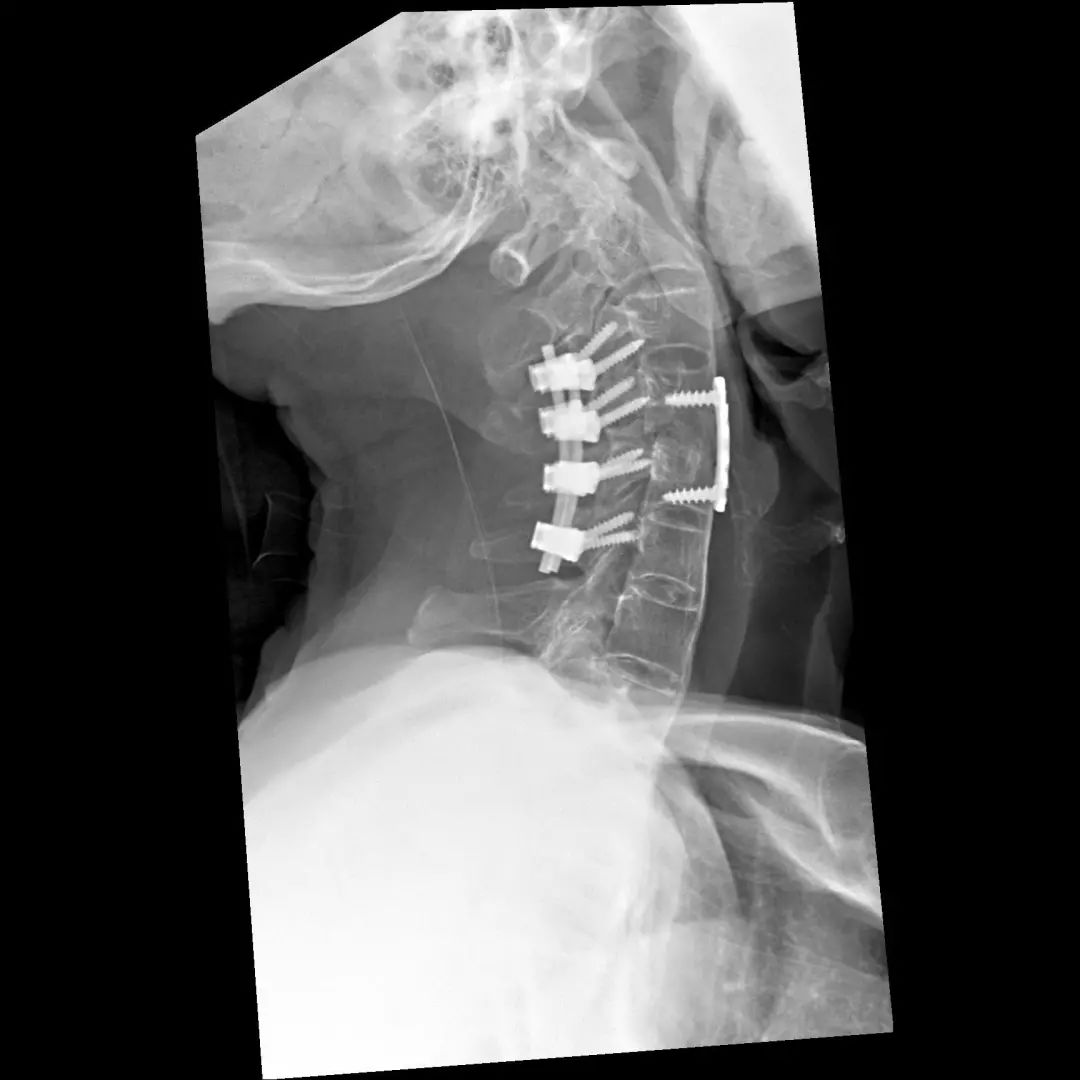

经过全程监护和系统治疗,患者术后恢复良好,骨折解剖复位,复查X线及CT显示固定位置佳,术后3天下地行走,术后4天即出院回家休养。

该手术为我市首例完成C1、2椎弓根钉棒系统固定手术,填补了枣庄在上颈椎外伤手术史上的空白,展现了枣庄市立医院脊柱外科不怕困难、勇于突破、积极向上的精神面貌,也是王存平主任技术高超、胆大心细的具体体现。